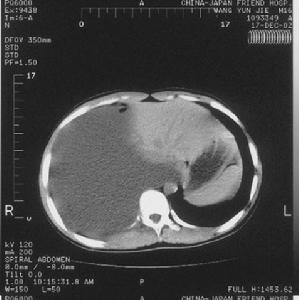

惡性胸腔積液CT圖(1)常規檢查:惡性胸腔積液一般為滲出液。滲出性胸腔積液的特點是蛋白含量超過3g/100ml或比重超過1.016在一些長期胸膜腔漏出液病人,由於胸腔內液體吸收的速率大於蛋白吸收的速率胸液內蛋白濃度也會增高,易與滲出液相混淆,所以檢查胸腔積液和血清中蛋白質和乳酸脫氫酶(LDH)水平,對於區分滲出液與漏出液有99%的正確性胸腔積液具有下列一個或多個特徵即為滲出液:①胸腔液體蛋白/血清蛋白>0.5;②胸腔積液LDH/血清LDH>0.6;③胸腔積液LDH>血清LDH上限的2/3。

惡性胸腔積液CT圖對引起胸腔積液的腫瘤的化療和放療有助於消除胸腔積液並改善呼吸道症狀。由淋巴瘤、肺癌及乳腺癌阻塞淋巴管產生的胸腔積液,放射治療可以去除阻塞病因,重建並改善胸液動力學,效果顯著。對於影響呼吸動力學威脅生命的胸腔積液在未找到其他有效治療方法之前胸腔穿刺有助於控制症狀。